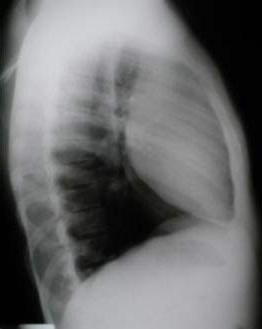

un paciente joven, con un gran tumor del mediastino anterosuperior de rápido

crecimiento, correlacionando su tamaño entre la radiografía

del tórax y los hallazgos tomográficos realizado 15 días

después, y las condiciones físicas al momento de su intervención,

con gran dificultad respiratoria.